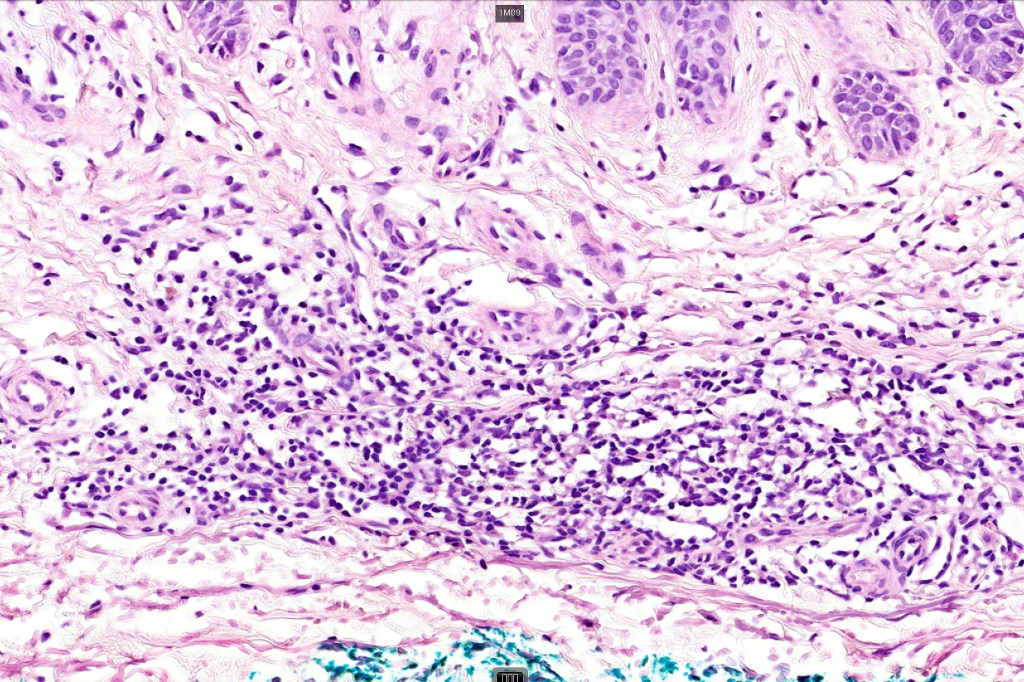

Histological features

•Most probably a localized inflammatory lesion rather than a true neoplasm

•Vascular dilatation in the dermal papillae and a perivascular sometimes neutrophil-rich infiltrate